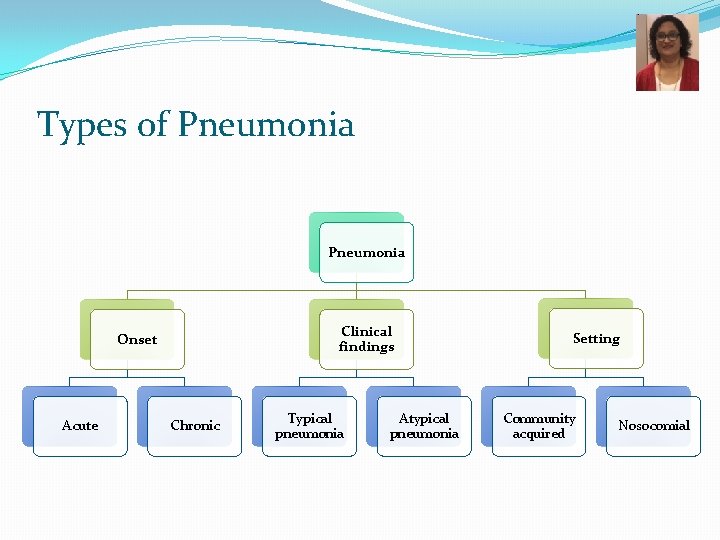

Types of Pneumonia Clinical findings Onset Acute Chronic Typical pneumonia Atypical pneumonia Setting Community acquired Nosocomial

Based on the setting in which the infection was acquired… Pneumonia NOSOCOMIAL COMMUNITY ACQUIRED ASPIRATION PNEUMONIA

Community acquired Typical vs Atypical pneumonia Typical Atypical Ø Pneumonia with typical features Ø C/F: high fever, chest pain, cough which is usually productive, shortness of breath, lobar consolidation on Chest Xray Ø Bacteria: � Streptococcus pneumoniae � Hemophilus influenzae � Klebsiella pneumoniae � Moraxella catarrhalis � Staphylococcus aureus Ø Pneumonia with atypical features Ø C/F: Less severe illness, dry cough, headache, and other systemic complaints, patchy bronchopneumonia Ø Bacteria: � Chlamydophila species � Mycoplasma pneumoniae � Legionella pneumoniae � Coxiella burnetii Ø Viruses

Causes of Nosocomial pneumonia Gram negative bacteria: Pseudomonas, Acinetobacter Klebsiella, E. coli, Serratia Gram positive organisms: Staphylococcus aureus Nocardia Fungi Aspergillus Mucor/ Rhizopus Viruses: CMV Risk factors • Recent hospitalization of at least 2 days • Nursing home or long-term care facility resident • Recent intravenous antibiotic therapy, chemotherapy or wound care • Ventilator-associated pneumonia • Post-transplant patients • Immunocompromised

Aspiration Pneumonia Inflammation of the lungs from inhalation of foreign material (food, liquids, vomit) or from fluids from the mouth. Microaspiration Pneumonia Occurs frequently in most people. Usually asymptomatic. � Predisposing conditions � Any condition associated with altered or reduced consciousness (e. g. after a stroke, while sleeping) � While vomiting � Condition causing abnormal gag and swallowing reflexes (e. g. neurological dysfunction) � Etiologic agents � Normal flora of oropharynx � Oral anaerobes: Prevotella, Fusobacterium spp. , Peptostreptococcus* � Streptococci * Anaerobes will be � Clinical presentation: covered in GERD � Chemical irritation � Due to toxic substances (e. g. gastric acid) � Bacterial infection (frequently polymicrobial) � Often necrotizing with fulminant course 8